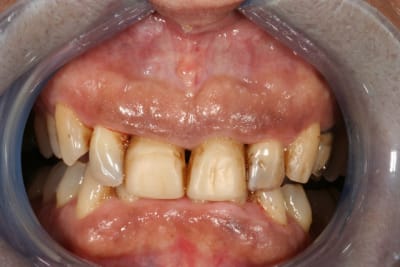

pour l'occlusion, voilà les photos, il y a effectivement une classe II, plus marquée à droite qu'à gauche

il y a l'absence de la 36 depuis quasiment l'enfance, l'occlusion est calée comme ça depuis plus de 30 ans et ça ne bouge pas

il n'y a pas (ou peu) de supraclusion (overbite je crois que c'est ça)

il n'y a aucun problème musculaire ou articulaire

elle a certes un sourire très gingival lié à la classe II, mais est-ce si grave que ça ?